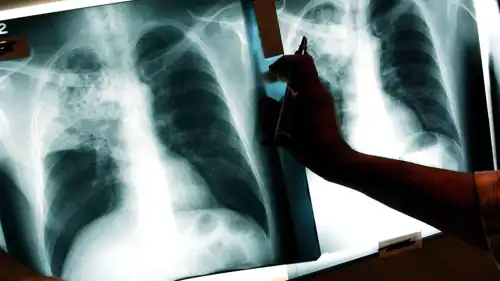

صورة أشعة لمريض بالسل